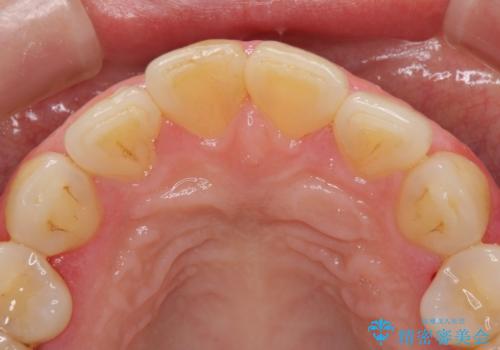

また、右上の前歯は裏側までヒビが入っていることや、1層構造のラミネートよりも2層構造のオールセラミッククラウンの方が色の再現性も高いことから、右上前歯1本のクラウン治療をおすすめしました。

今回は、歯肉炎があるため、その治療を行ってからクラウンを製作しました。

歯肉炎がない場合は、1か月ほどで治療が完了します。逆に、炎症がひどい場合は、治療期間が長くなります。